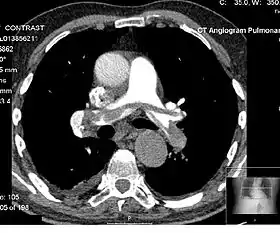

Angiography

Computed tomography angiography (CTA) is a type of contrast CT to visualize the arteries and veins throughout the body.[37] This ranges from arteries serving the brain to those bringing blood to the lungs, kidneys, arms and legs. An example of this type of exam is CT pulmonary angiogram (CTPA) used to diagnose pulmonary embolism (PE). It employs computed tomography and an iodine-based contrast agent to obtain an image of the pulmonary arteries.[38][39][40]